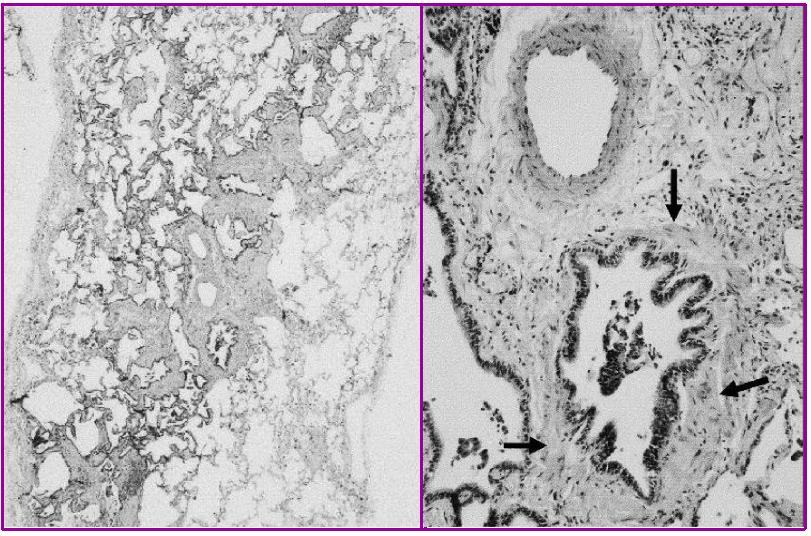

之后进行病理检查:肉芽肿,纤维化,细支气管炎,病理结果符合过敏性肺炎的表现,但是还没有问出病史。

ZYM:肉芽肿,NSIP-like,细支气管炎亚急性表现细胞性NSIP、细支气管炎和肉芽肿三联征,出现<75%。

急性HP:急性纤维素性机化性肺炎。

CLX:慢性HP,纤维化比较明显,肺结构也被破坏,肉芽肿,UIP-lilke,细支气管炎。

慢性HP:气道中心性肺纤维化较明显。

下图都是肉芽肿性疾病,但是结节病的肉芽肿是边界非常清楚的间质性结节,过敏性肺炎的肉芽肿的边界比较模糊。